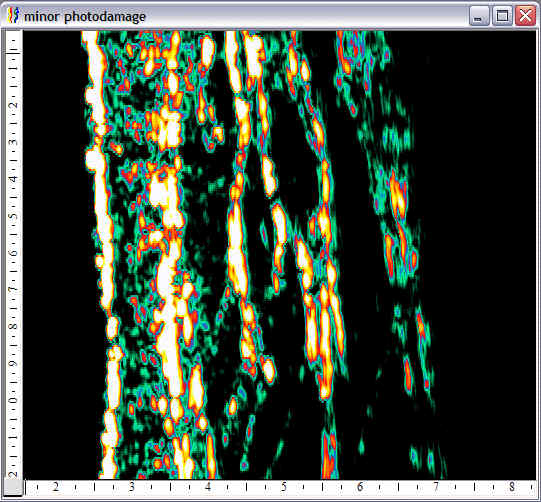

Face, minor photoaging |

Face, major photoaging |